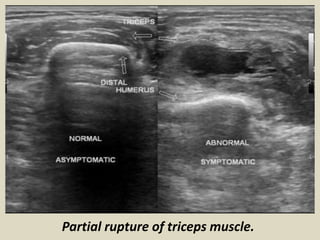

The rupture of the triceps tendon usually results

from a fall with an outstretched hand. A bone

fragment may remain attached to the tendon

(avulsion). Ultrasound shows a retracted tendon

surrounded by fluid. Partial ruptures produce a

small fluid-filled or an hypoechoic area in the

tendon .

Partial rupture of triceps muscle.